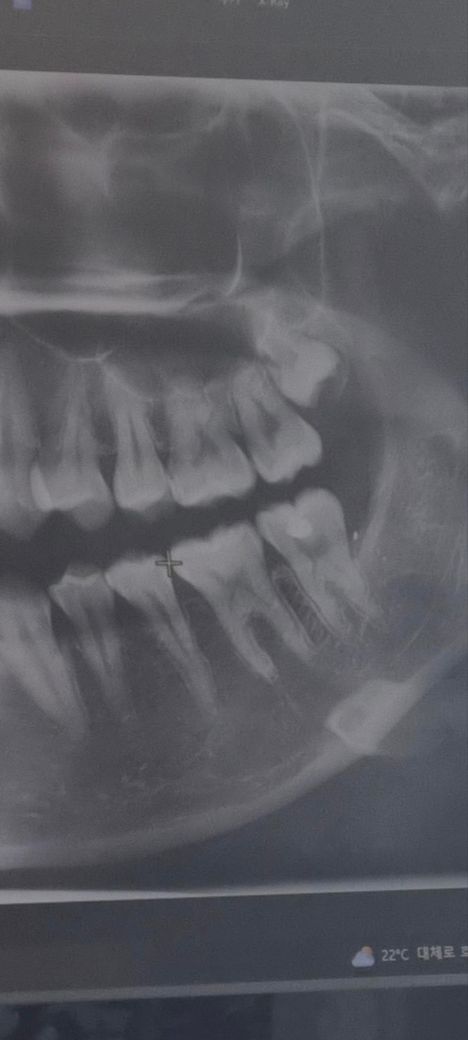

[사진첨부] 이 사랑니 뽑을 수 있는건가요?

사진은 지난 5월달에 치과 내원 했을 당시에 촬영한 엑스레이 사진입니다.

• 1번 째 사진

• 사랑니로 인해서 불편감이 생길 수도 있습니다. 일반 치과에서는 빼기힘들지만 대학병원 가시면 지금 상태에서도 아마도 뽑아줄 것으로 보입니다.

• 아직 20대 초반이라면 사랑니가 조금 더 내려올 여지는 있습니다. 현재 발치를 하고자 한다면 잇몸째고 매복 사랑니에 준해 발치를 하게 되고, 상악동과 가까워 발치 중 상악동 천공의 가능성도 있습니다. 턱 통증과는 큰 연관이 있을지는 모르겠습니다. 발치 중 너무 오래 턱을 벌리고 있다보면 턱이 아플 순 있습니다.

• 사진에 보이는 사랑이는 매복되어 있고 크게 문제를 발생시키지 않기 때문에 불편감이 생길 가능성은 매우 낮습니다 턱이 불편하다면 사랑니 때문이 아니라 턱관절 질환으로 인해서 불편할 가능성이 높습니다 턱관절 질환을 치료하기 위해서는 체코에서 진료를 받아 보는 것이 좋을 수 있습니다 자세한 확인을 위해서 치과에서 진료를 받아 보세요